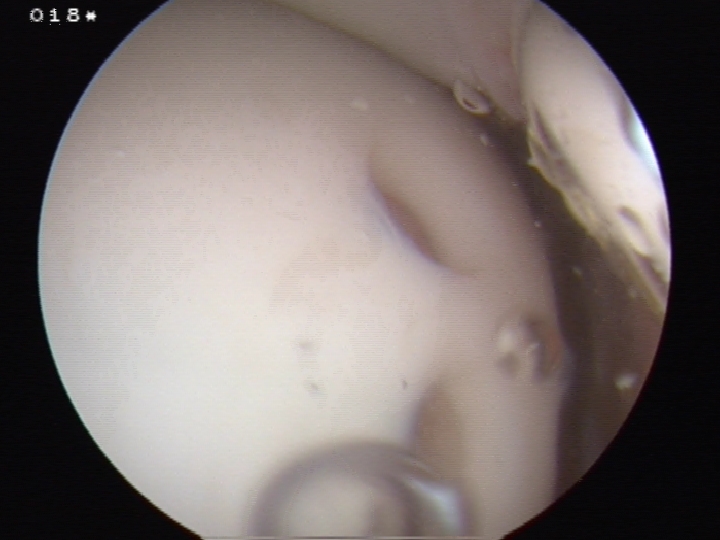

Fibrocartilage response to microfracture

Technique

Debride all unstable cartilage to stable edge

- removed calcified cartilage layer with curette, protect subchondral bone

- create a perpendicular edge which helps to hold the clot

Arthroscopic microfracture awl / 1.6 mm drill

- typically 3-4 mm apart

- depth until see fat globules